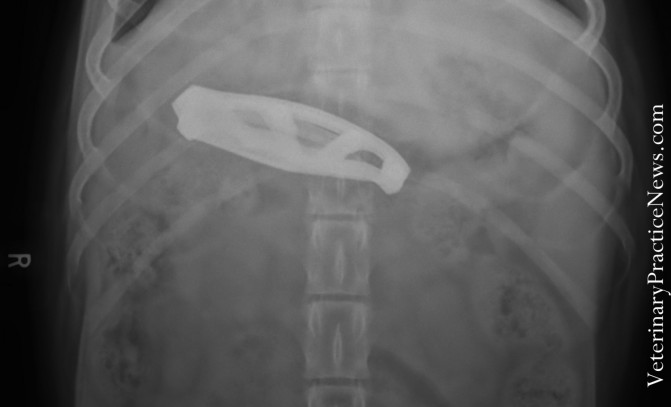

Mégsem a csenőmanók vittél el a fél pár zoknikat

Ha lenne kutyánk, akkor most biztosan elkezdenénk aggódni érte, mert hiányzó fél pár zokniból elég jól állunk. Egy dán dogról azután derült csak ki, hogy egész komoly mennyiséget tett magáévá, hogy hányni kezdett, majd állatorvoshoz vitték. Összesen 43,5 darab csúszott le a torkán, mielőtt észrevették és megmentették.